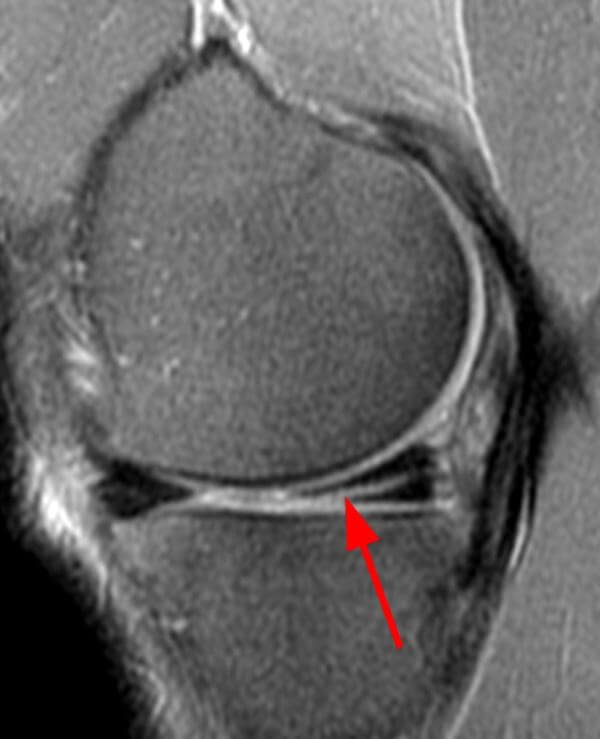

Le ménisque n’est pas visible sur une radiographie. Le meilleur examen pour confirmer une lésion de ménisque est la résonance magnétique (RMN).

Il ne faut pas oublier que l’espace articulaire, entre le fémur et le tibia est fort étroit. Quand un fragment de ménisque se détache, celui-ci se coince entre ces deux os. Le genou devient douloureux, il se gonfle et on a des difficultés à le plier ou à l’étendre.